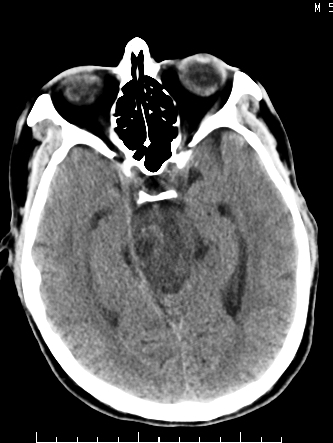

m/50,头昏头痛1月,近3天感觉左半肢体活动不利,自述半年前呈患肺tb,腰穿脑脊液未见特殊改变。现做头颅ct请大家会诊。

脑干区胶质瘤可能性大。

考虑:1.结核脓肿,2.星形胶质瘤,但脑积液正常,这考虑肿瘤的可能性大些.期待结果

首先考虑肿瘤性病变,星形细胞瘤可能性大,不排外转移瘤。建议mri。

脑干占位,考虑转移瘤可能性大,不除外胶质瘤.

请大家结合临床表现看一下 左侧肢体的症状是脑干 还是其他的问题 另外结核感染脑脊液应该有问题 所以应该考虑肿瘤性病变

可考虑结核,患者水肿范围大,囊性病灶边缘密度较高,不考虑胶质母细胞瘤